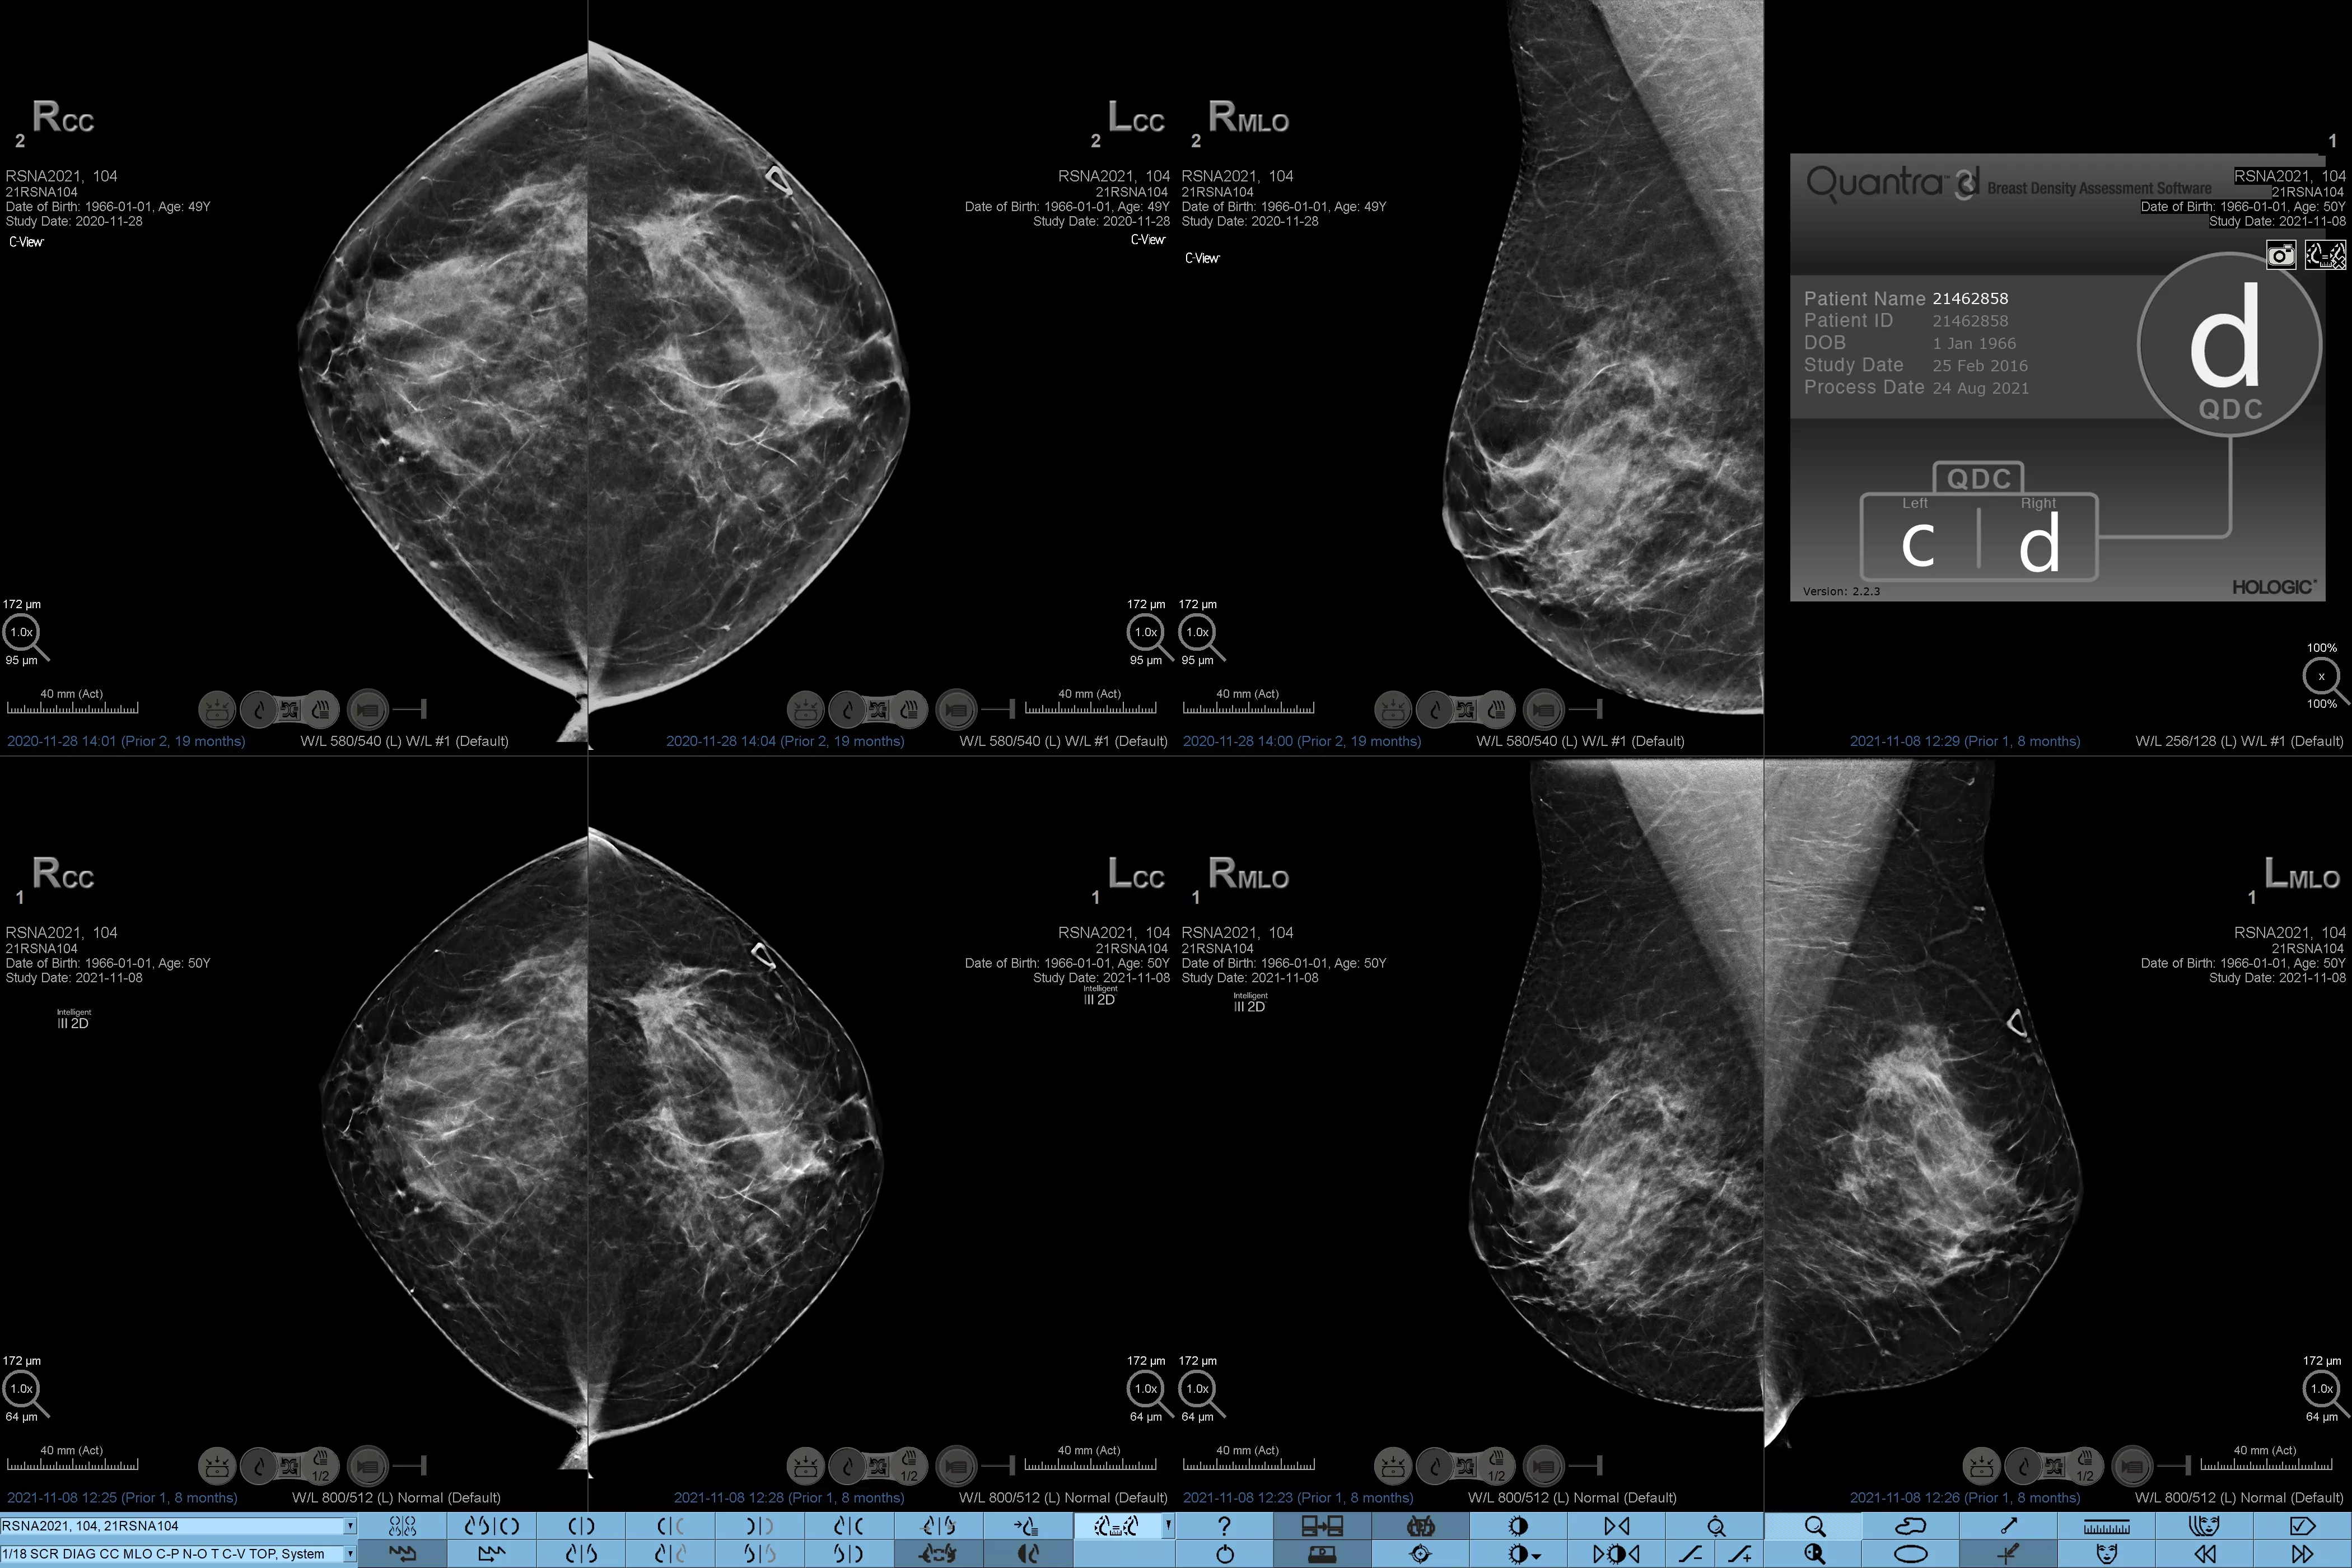

Man ved, at højere brysttæthed øger en kvindes risiko for brystkræft.1 Behovet for nøjagtige, objektive analyser er derfor afgørende. Quantra-teknologisoftwaren er drevet af maskinlæring og analyserer både 2D™ og tomosyntesebilleder for fordeling og tekstur af parenkymvæv. Den kategoriserer bryster i fire brystkompositionskategorier i overensstemmelse med vejledningen fra American College of Radiology (ACR) BI-RADS Atlas 5th Edition.2

* Scorer er baseret på ACR BI-RADS-kategorier på linje med den reviderede vejledning fra American College of Radiation (ACR) BI-RADS Atlas 5th Edition. Dette tager højde for mønster og tekstur i sammenlignet med volumen, når man bestemmer tæthed.

8. Breast composition categories as described in ACR BI-RADS Atlas.